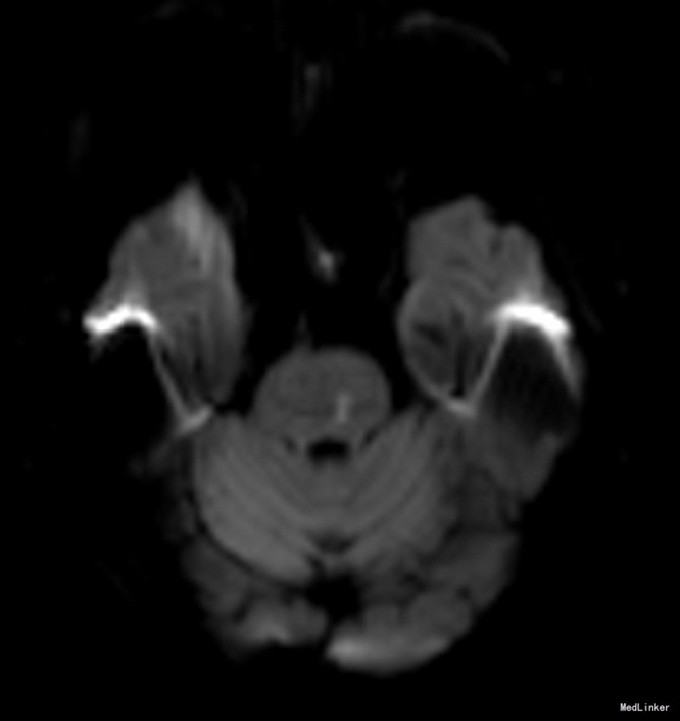

老年女性,急性起病。查体可见左眼内收受限,双眼右视时有水平眼震。影像学提示左侧桥脑背侧梗塞。与临床相符。考虑前核间性眼肌麻痹。 附上另一例前核间性眼肌麻痹头MRI,如图: